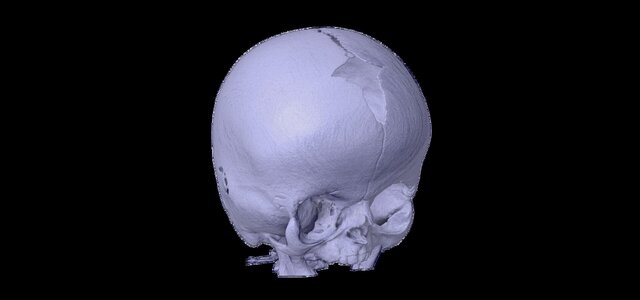

# Advanced 3D Modeling and Printing for Neonatal Apert Syndrome I led and supervised a dedicated team in reconstructing a highly precise neonatal cranium model for a patient affected by Apert syndrome, leveraging advanced HRCT data and parametric modeling techniques. Through meticulous analysis and collaborative innovation, we converted complex imaging data into a detailed 3D model that accurately represented the unique cranial anatomy of the patient. The model was then expertly 3D printed, serving as a critical surgical aid to enhance preoperative planning and precision during the procedure. This achievement underscores the transformative potential of integrating medical imaging with cutting-edge modeling and printing technologies to address complex craniofacial conditions, setting a benchmark for future interdisciplinary collaborations. For example, the detailed 3D representation allowed surgeons to simulate surgical approaches, reducing risks and ensuring better outcomes for the patient.